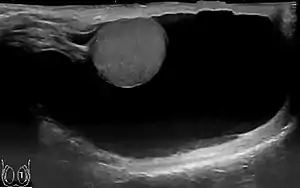

| Scrotal ultrasound of a 10 cm large hydrocele, with anechoic (dark) fluid surrounding the testicle | |

The swelling is soft and non-tender, large in size on examination, and the testis cannot usually be felt. The presence of fluid is demonstrated by transillumination. These hydroceles can reach a huge size, containing large amount of fluid, as these are painless and are often ignored. They are otherwise asymptomatic, other than size and weight, causing inconvenience. However the long continued presence of large hydroceles causes atrophy of testis due to compression or by obstructing blood supply. In most cases, the hydrocele, when diagnosed early during complete physical examination, are small and the testis can easily be palpated within a lax hydrocele. However Ultrasound imaging is necessary to visualize the testis if the hydrocele sac is dense to reveal the primary abnormality. But these can become large in cases when left unattended. Hydroceles are usually painless, as are testicular tumors. A common method of diagnosing a hydrocele is by attempting to shine a strong light (transillumination) through the enlarged scrotum. A hydrocele will usually pass light, while a tumor will not (except in the case of a malignancy with reactive hydrocele).

The accuracy of the diagnosis must be ascertained. Great care must be taken to differentiate a hydrocele from a scrotal hernia or tumor of the testicle. Ultrasound imaging can be very useful in these cases. A hernia usually can be reduced, transmits a cough impulse, and is not translucent. A hydrocele cannot be reduced into the inguinal canal and gives no impulse on coughing unless a hernia is also present. In young children a hydrocele is often associated with a complete congenital type of hernial sac.